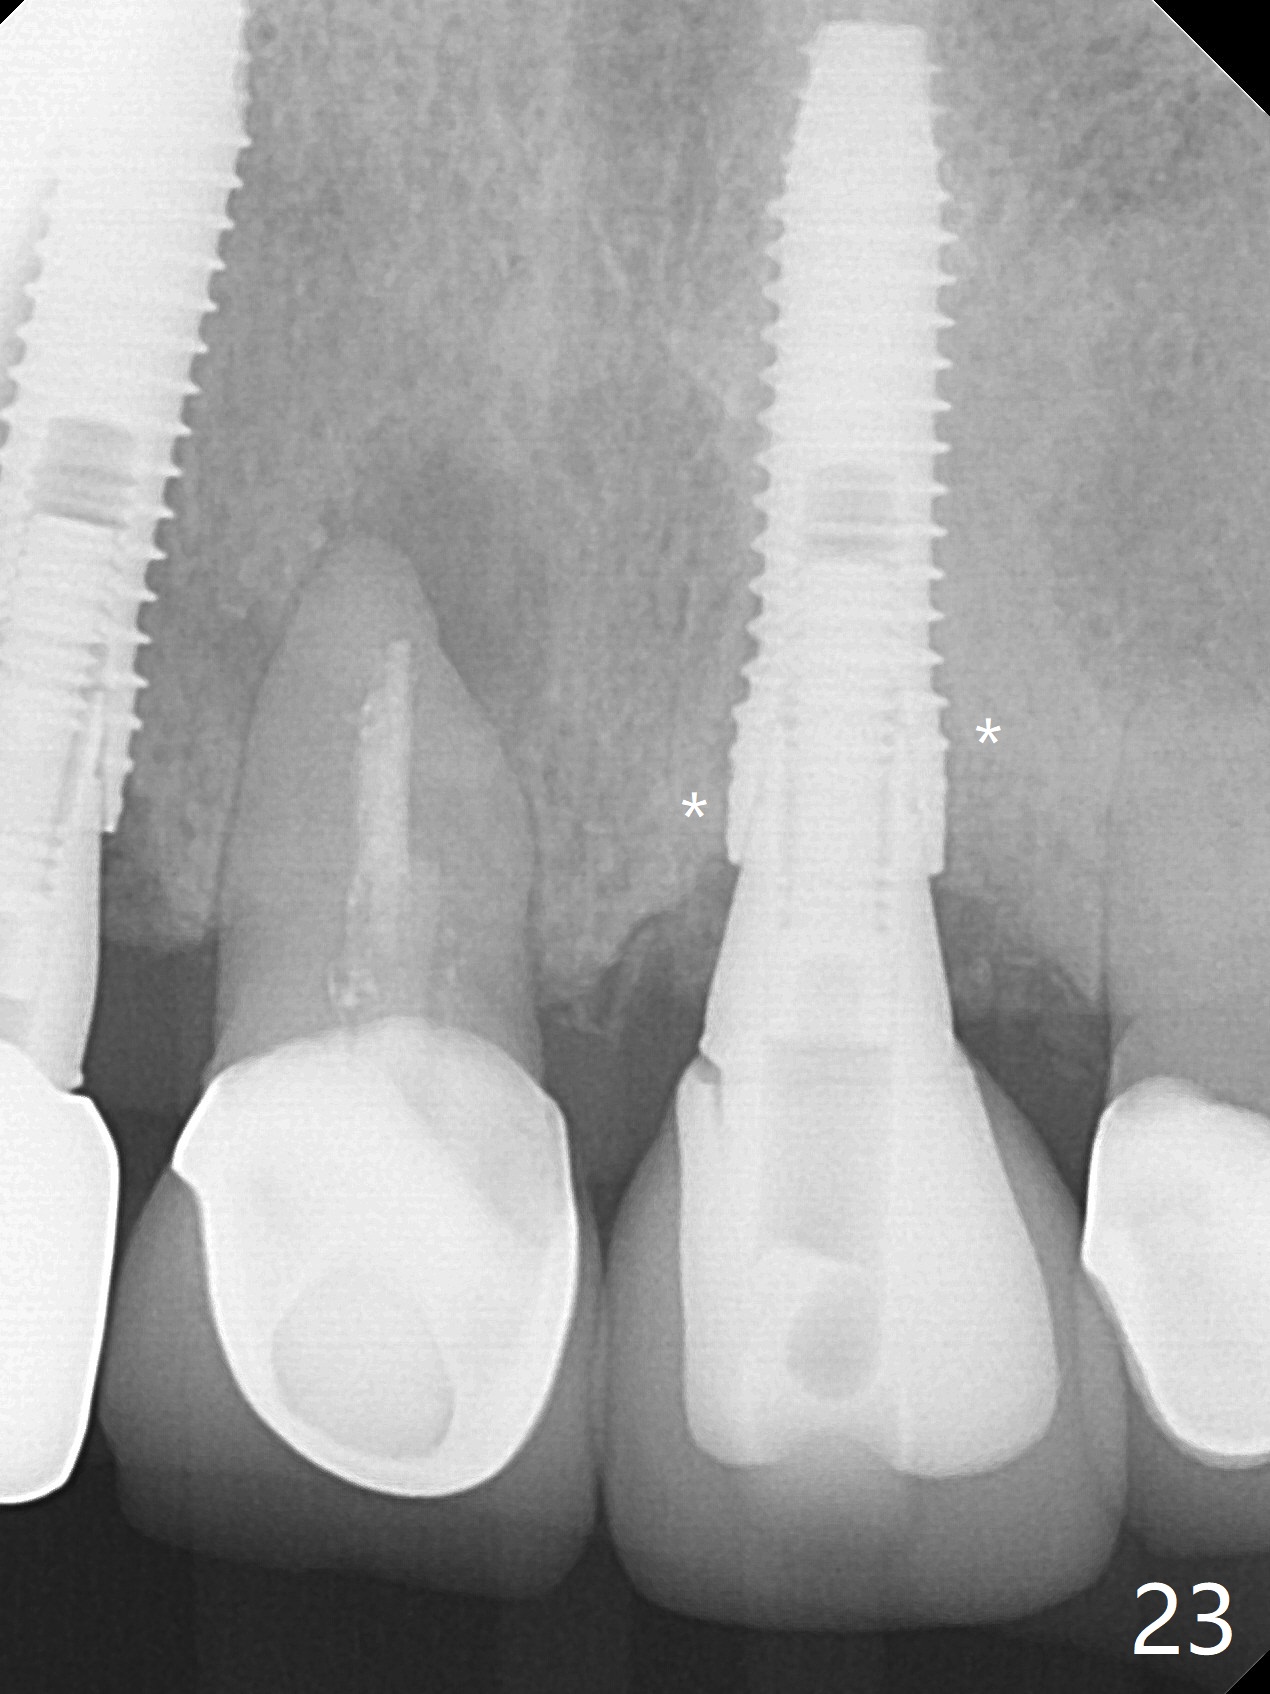

Nasal Floor

The buccal contour at #9 seems to be slightly concave preop (Fig.1,2 (*)). In fact the buccal plate is found to be lost when the tooth is extracted. Osteotomy is initiated as palatal as possible apical, but the occlusion dictates the coronal end of the osteotomy should be buccal, leaving the buccal gap ~ 2 mm for bone graft. The initial osteotomy (18 mm deep) appears to be close to the Incisive Foramen (Fig.3 blue dashed line). The nasal floor appears to be intact when the drill is removed. Subsequent osteotomy is adjusted so that the apical end of the osteotomy moves distal; when a 3.8x15 mm dummy implant is partially placed, there is clearance (Fig.4). It remains so when a definitive implant is seated (Fig.5); Vanilla graft is placed (Fig.5 *) before placement of a 4.5x5.5(3) mm abutment. More allograft is placed when an immediate provisional is fabricated (Fig.6 arrow and *). The gingiva remains to be recessive 1 month postop (Fig.7). It seems to be related to the bulky gingival margin of the provisional (Fig.8 *). After trimming the latter (Fig.9 *), the gingival margin immediately returns close to normal (Fig.10). The gingival margin is even between #8 and 9 two months postop, but the bone graft is exposed apically (Fig.11 ^). It may heals by itself. Otherwise debridement, regraft, PRF and suture are pending. The coronal portion of the socket heals 4 months postop (Fig.12). The gingival cuff forms by the immediate provisional (which is removed for impression) 4 months postop (Fig.13 *). While the full Zirconia crown at #7 remains intact (Fig.14), the PFM at #9 has porcelain chip (Fig.15). It is partially due to the occlusion; while the crown at #7 has clearance with the opposing dentition (Fig.16 *), the one at #9 has no. The access hole at #9 (Fig.17 *) seems to weaken the crown structure. There is no access hole at #7. No solid posterior support is another contributing factor for chip (Fig.18). The buccal plate has mild atrophy at #7 and 9 (Fig.19 *). A piece of bone graft is being expelled apically at #9 (Fig.20 >) and is removed subsequently (Fig.21). Before impression for repacking porcelain, the opposing incisal edge has been shortened (Fig.22 arrows, as compared to Fig.16). Since the ideal access hole is at the incisal edge (Fig.25 black circle), buccal to the existing one (Fig.24 A), the abutment is torqued before the repaired crown is recemented (Fig.23). Finally the crown has occlusal clearance (Fig.26). Porcelain chips again around the access hole of PFM 1.5 years post 2nd cementation. The dense bone at the crest (*) cannot explain why the abutment is not loose, since it remains incompletely seated (>). As it was trimmed short, an angled abutment is used (Fig.28). The coronal end is lingual, while #9/24 is edge to edge. The lingual aspect of the coronal end of the abutment is heavily trimmed to reduce bulkiness. To prevent chip, Zirconium crown will be fabricated in spite of the fact that it does not match the PFM of #8 (potential shade discrepancy). The patient is pleased with the new Zirconia crown (Fig.29).